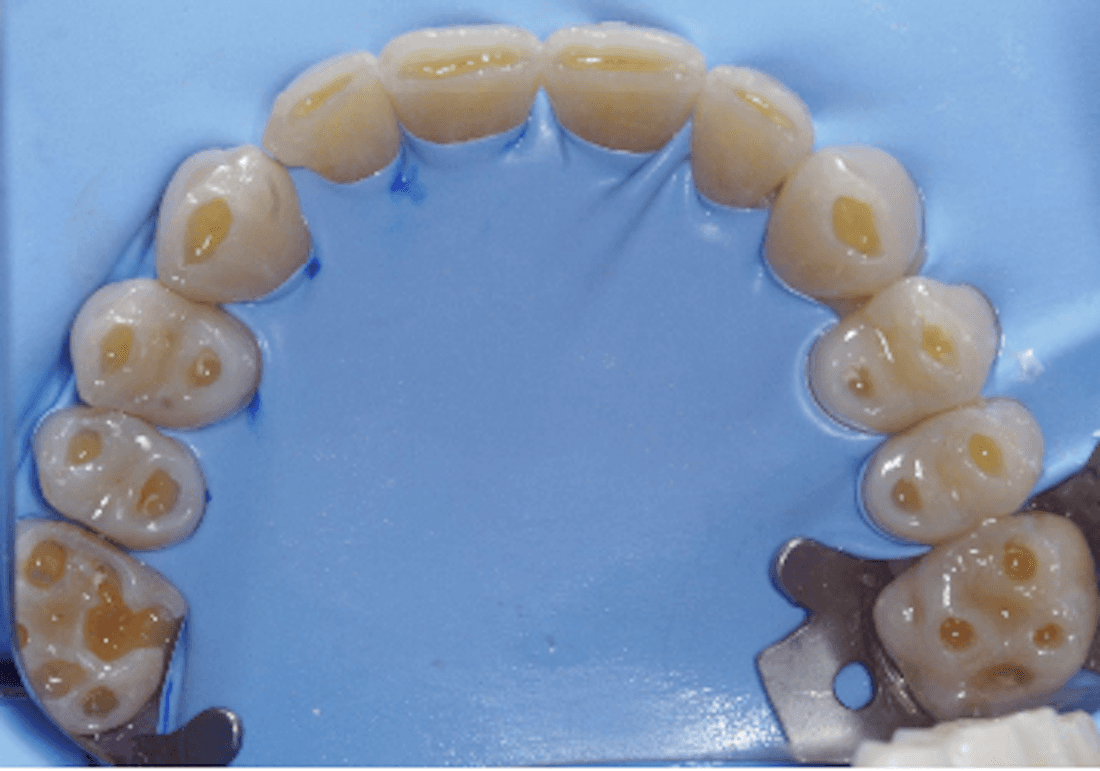

Another dentist told him he needed crowns on all his teeth. Now, all these lesions have been restored with a highly wear- and acid-resistant restoration.